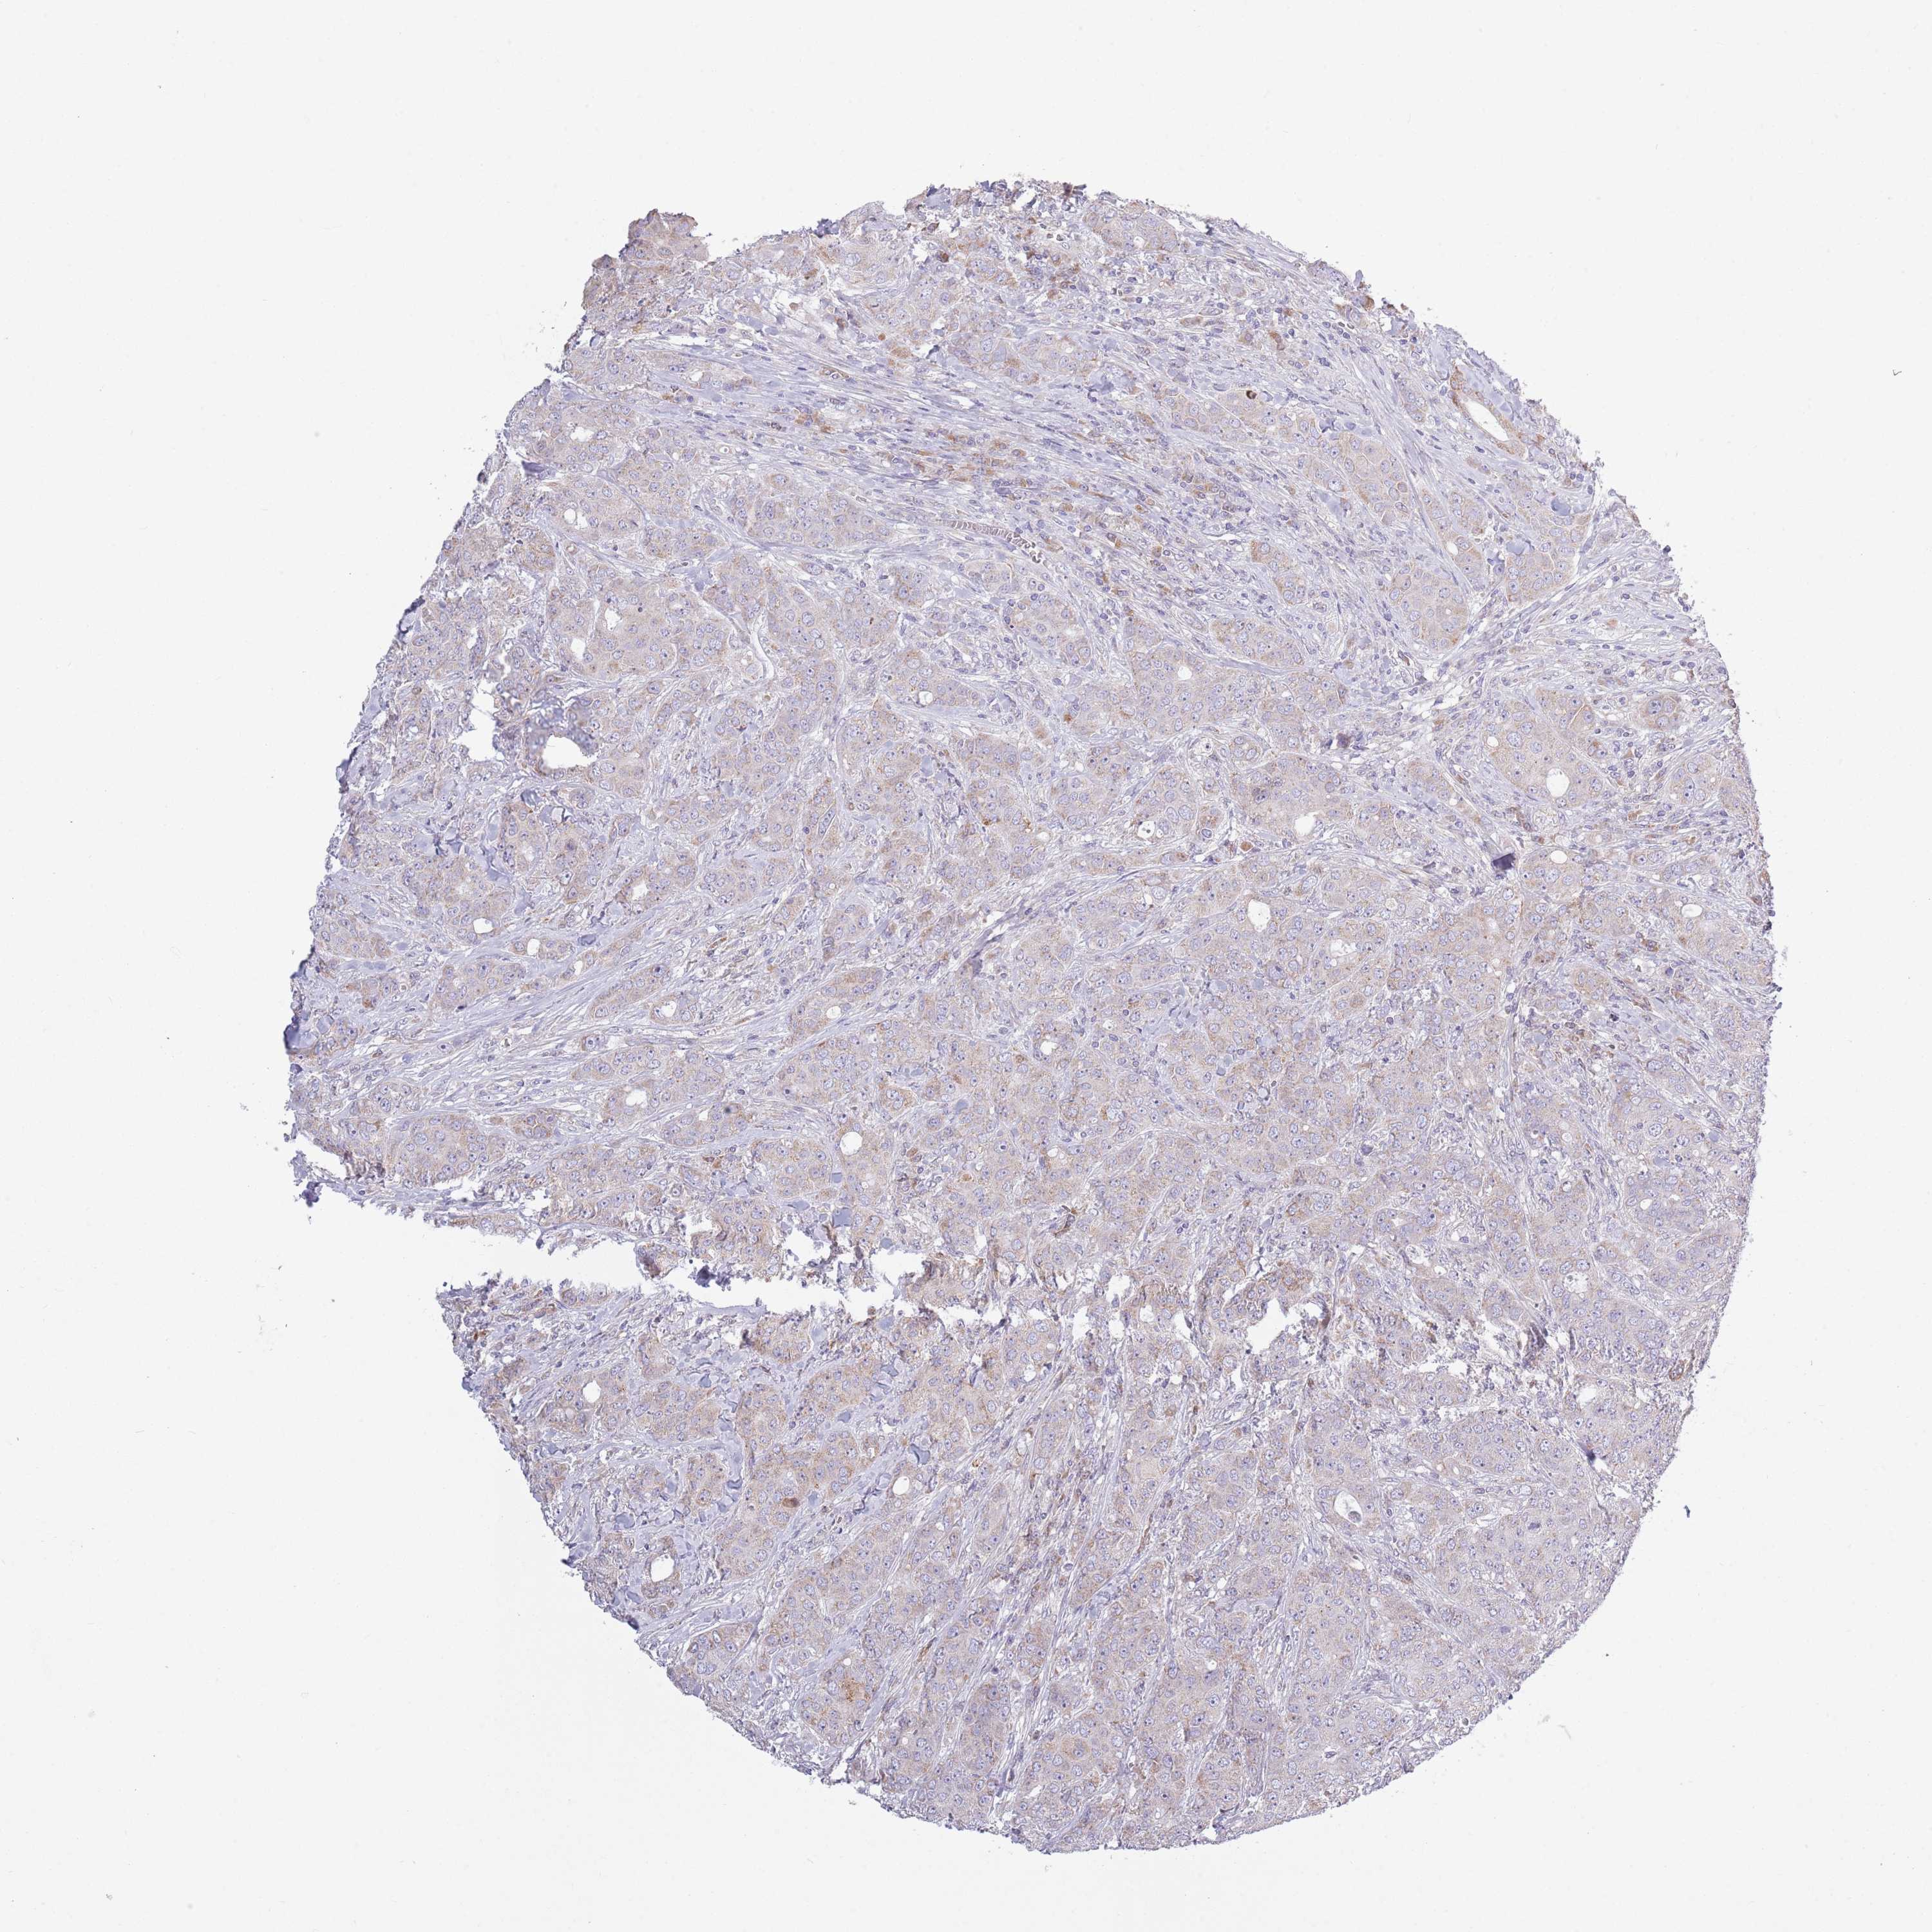

BRCA TCGA BRCA VALIDATION PROTEIN EXPRESSION